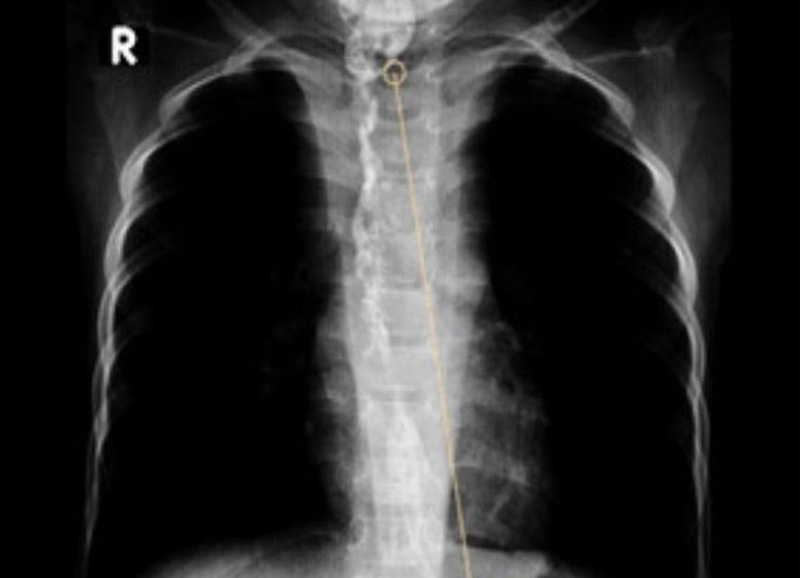

Trẻ phải mở dạ dày và đặt ống nuôi ăn. Ảnh: BVCC

Đơn cử như trường hợp bé T.Đ., vì nhầm lẫn nước tro tàu trong chai là nước suối nên đã vô tình uống phải. Bé được đưa đến bệnh viện và được bác sĩ tận lực cứu chữa, nhưng vẫn bị hẹp toàn bộ thực quản ngực. Không thể ăn bằng đường miệng, bé phải mở dạ dày và đặt ống nuôi ăn.

Trải qua nhiều lần nong thực quản, mổ cắt nối thực quản nhưng vẫn tái hẹp, em phải phẫu thuật thay thế thực quản bằng dạ dày. Hiện, bé đã ăn uống lại được nhưng vẫn tiếp tục tái khám, theo dõi.